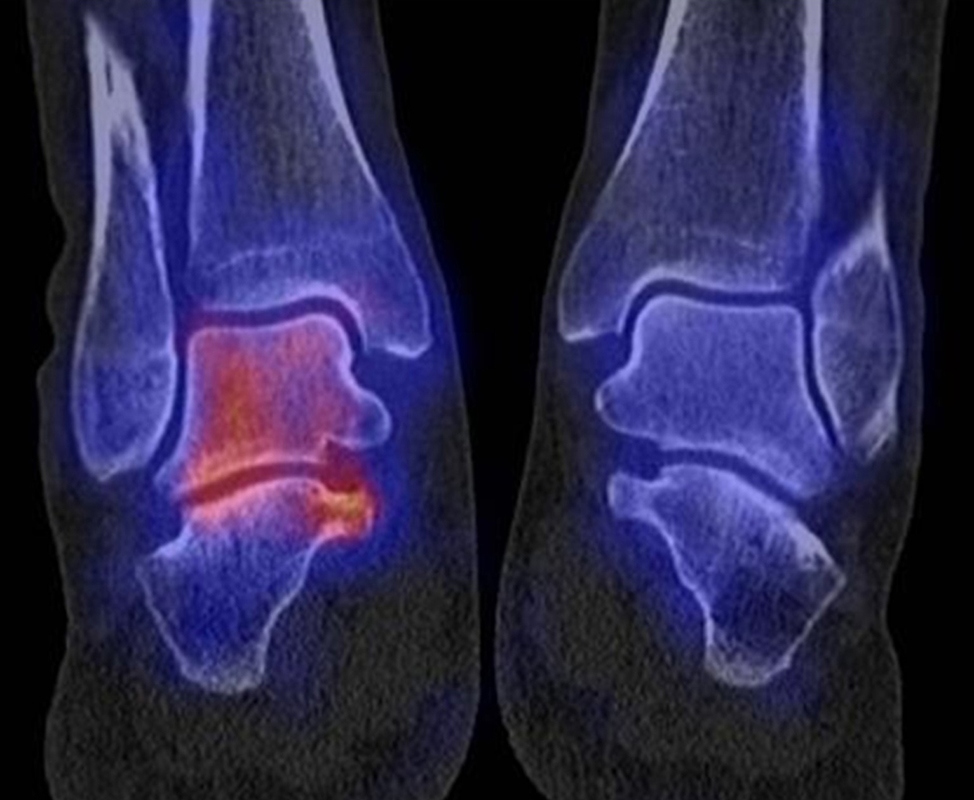

Abbildung 1.2. zeigt eine ausgedehnte posttraumatische Arthrose im linken OSG. Der metabolische Focus liegt in der Hauptbelastungszone.

Abbildung 1.8.a und b: Akute Arthritis bei bekannter Gicht in beiden OSG: links die Früh-/Weichteilphase; rechts die Mineralisations­phase. Deutliche, entzündlich bedingte Mehranreicherungen in der Früh-/Weichteilphase. In der Mineralisation­sphase erkennt man die entzündliche Mitreaktion der subchondralen Gelenkabschnitte.

Abbildung 1.8.c - e: Akute Arthritis in beiden OSG, rechts > links. Im SPECT/CT erkennt man die Mitreaktion der subchondralen Gelenkabschnitte. Die Arthritis ist so akut, dass (noch) keine ossären morphologischen Veränderungen im CT abgrenzbar sind.